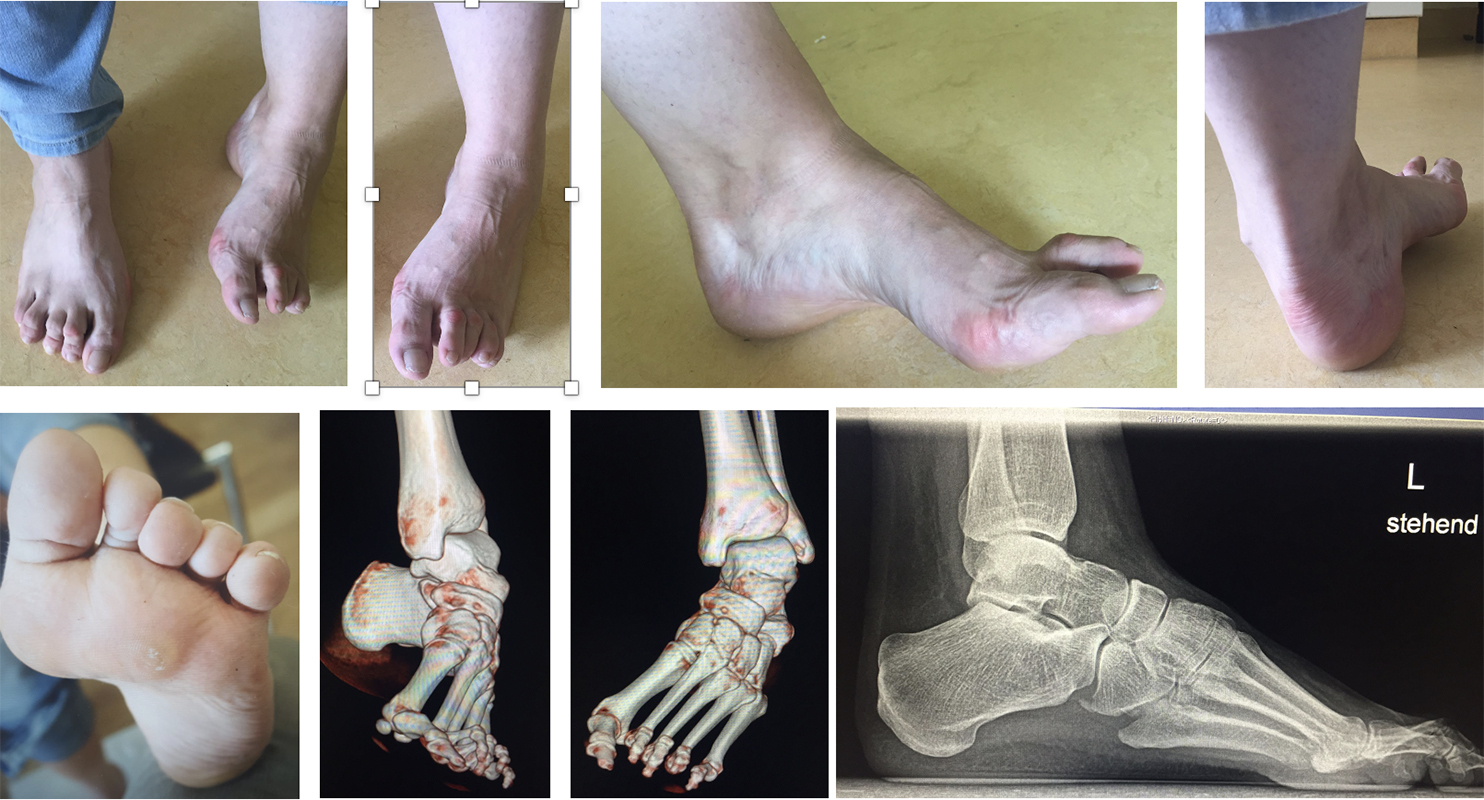

Abb. 40 a-f: Kompletter klinischer und radiologischer Verlauf eines schweren Ballenhohlfußes: Bild im Stand mehrere Ansichten sowie radiologische Diagnostik präoperativ (a), percutane Ablösung der Plantarfaszie als ersten operativen Schritt (b), radiologisch sichtbare Osteot0mien MT I-V sowie klinisches Ergebnis intraoperativ (c-d), klinische Gegenüberstellungen der präoperativen Fehlstellung und der postoperativen Korrektur (e); zweites Beispiel eine spastische Hohlfußfehlstellung im prä- und postoperativen klinischen Verlauf (f).

Zum Lesen der Bildbeschreibung und zur Vollansicht bitte die Bilder anklicken. Bilder: A. Helmers.